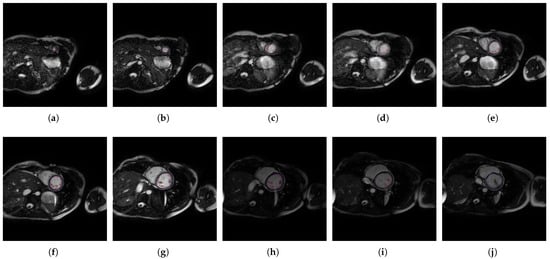

2. Methods

2.1. A Software Tool to Quantify the Trabeculae Degree in the LV Myocardium for a Population of Patients with Genetic Cardiomyopathies (QLVTHCI)

- The different MSERs are detected in a centered ROI of each input image by the use of OpenCV [23]. As the LV cavity is normally represented by a circular shape, the centroid of each MSER detected is computed in order to automatically identify the left ventricle cavity anywhere in the image and for applying the convex hull.

- The previous application of the convex hull allows a second refining to optimize the search process of the external layer and the trabeculae areas. The parameter e-expand is redefined and adjusted to accurately determine the external layer of the compact zone, thanks to plotting several lines from the centroid of the LV to reach the points of the external layer. This parameter establishes the distance of the lines between the centroid of the LV cavity and the possible space where the external layer can be found, taking into account the particular features of genetic cardiomyopathies. We optimized the parameter e-expand for different situations or possible cardiomyopathies.

2.5. Magnetic Resonance Protocol

| Hospital | HMC | UHVA |

|---|---|---|

| Analysis | AW4.3-08 | View-Forum 6.3 |

| Scanner | 1.5 T scanner | 1.5 T magnet |

| Provider | General Electric Systems | Philips Medical Systems |

| Repetition interval | 3.8 ms | 3.3 ms |

| Echo time | 1.7 ms | 1.7 ms |

| Flip | 60° | 60° |

| Matrix | 224 × 224 | 192 × 256 |

| Echo train length | 23 | 23 |

| Cutting thickness | 8 mm | 8 mm |

| Space between slices | 2 mm | 2 mm |

| Phases | 20 | 20 |